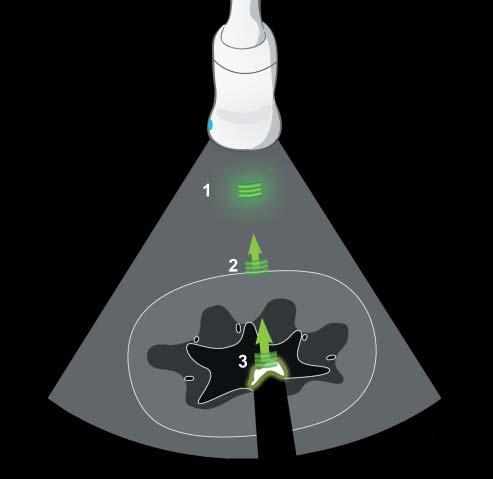

Interactionsbetweenultrasoundwavesandtissues andmaterialsvary,dictatingtheintensityofechoes generatedandtheresidualintensityofthepulsethat pursuesitscoursethroughtissues(Hangiandreou etal.2003)(Figure1.3).Forinstance,ultrasound wavespenetratingfatresultin acousticdiffusion,or scattering,astheprimaryinteraction,reducingthe

intensityoftheinitialpulse.Thistypeofinteraction alsoexplainstheechotexture–i.e.,granularity–ofthe parenchymathatvariesamongorgans.Ontheother hand,theinteractionwithasmoothinterfacethat isperpendiculartothebeamaxis,suchastherenal capsuleinFigure1.3,causes specularreflection,which producesintenseechoesintheoppositedirectionof theinitialpulse.Somematerialslikemineralabsorba significantcomponentoftheinitialpulseenergythat becomestooweaktogenerateechoesfromdeepertissues.Ultrasound absorption canthencauseashadow (seethesection“Artifacts”).Finally,ultrasoundwaves maychangeindirectiondueto refraction.Inreality, thesetypesofinteractionsareoftencombinedand theirpresenceandrelativeimportanceismainly influencedbythedifferencesinacousticimpedance andbytheshapeofthetissue(ormaterial)interfaces. Theseinteractionscausetheemittedultrasoundpulse energytoeventuallybecomecompletelydissipated.

Figure1.3. Interactionsbetweenultrasoundwavesand tissues. Theemittedultrasoundpulseischargedwithenergy. Inthisexample,thepulseinitiallyinteractswiththeabdominalfat(1),causingacousticdiffusion(greenhalo)andpartly losingitsenergyasitcontinuesitscourse.Wheninteractingwithasmooth,linearinterfacesuchastherenalcapsule (2),astrongspecularreflectionoccursthatgeneratesahighly intenseecho(greenarrow).Theweakerultrasoundpulsethen reachestherenalpelviccalculus,whichabsorbsmostofthe waveenergywhilecausingastrongreflection(greenarrow). Anacousticshadowisgeneratedandtheinitialpulseenergy iscompletelydissipated.